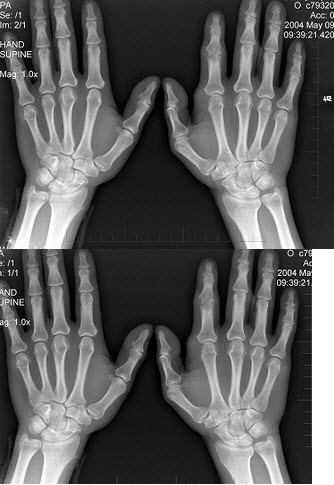

36、单项选择题

女,50岁,手指关节肿痛,晨僵,结合图像,最可能诊断是()

A.关节结核

B.牛皮癣性关节炎

C.痛风性关节炎

D.类风湿关节炎

E.Reiter综合征

79、单项选择题

男,19岁,双手肿痛2年,晨僵,结合图像,最可能诊断是()

A.痛风

B.强直性脊柱炎

C.类风湿关节炎

D.退行性关节炎

E.未见异常